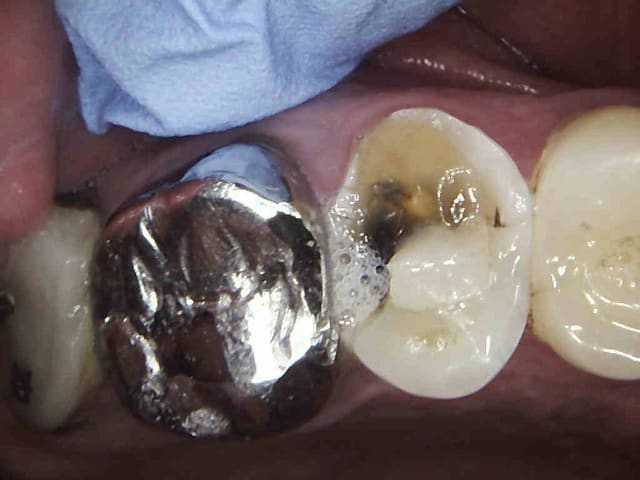

Ton plombier et ses 80 euros peut aller se rhabiller, patiente CMU encore, je ne pense pas que des composites à 2 balles soient indiqués.

2 v0xtrf - Eugenol

3 lwdn4a - Eugenol

1 uql9qu - Eugenol